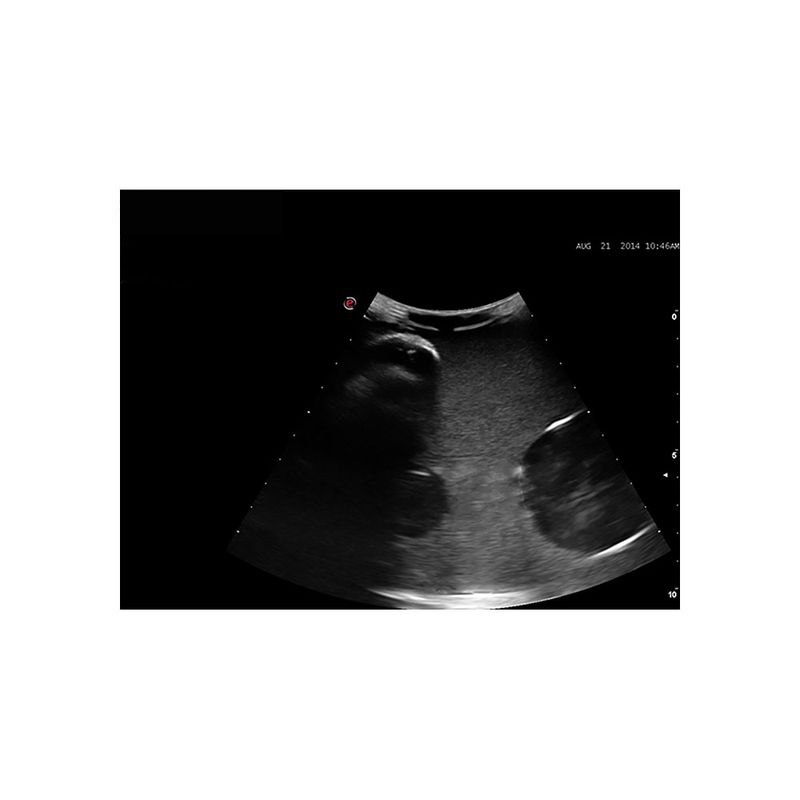

超声引导下囊肿穿刺引流模型

型号:PC-BP030

模型为培训超声引导下囊肿穿刺引流而专门设计的模型,适用于外科以及超声影像科的教学与培训。